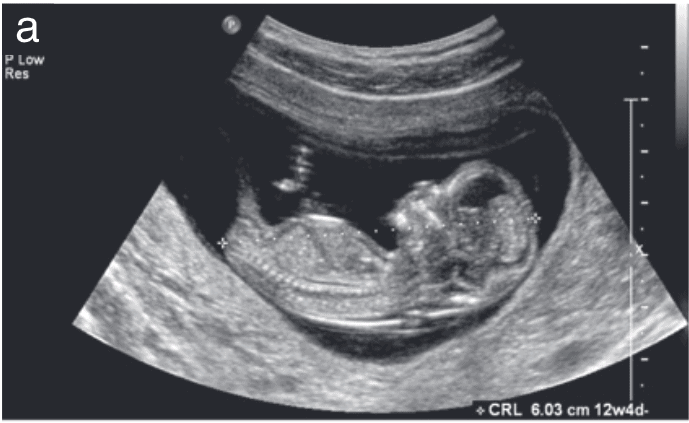

In today's technologically advanced world, obstetric ultrasonography has become a beacon of hope and clarity for mothers like Meera. This non-invasive imaging technique uses sound waves to create images of the developing fetus, providing critical insights into the baby's health and development.

Obstetric ultrasonography addresses these emotional concerns by providing tangible evidence of the baby's well-being. Each ultrasound session transformed Meera's anxiety into comfort as she watched her baby's tiny heart beating and witnessed the little kicks and stretches on the screen. The detailed images offered her a glimpse into her baby's world, bridging the emotional distance and reinforcing the bond between mother and child.

Imagine Meera's relief when, during one of her ultrasound sessions, the sonographer pointed out her baby's healthy heartbeat and even managed to capture a glimpse of the baby sucking its thumb. These moments were more than just medical evaluations; they were milestones that strengthened her confidence and peace of mind.

The reassurance provided by obstetric ultrasonography extends beyond just the emotional realm. Practically, it plays a crucial role in monitoring the baby's growth, detecting any potential complications early, and guiding necessary interventions. For instance, Meera's sonographer identified a minor issue with the baby's positioning early on, allowing her doctor to recommend exercises that helped correct it, ensuring a smoother delivery process later.